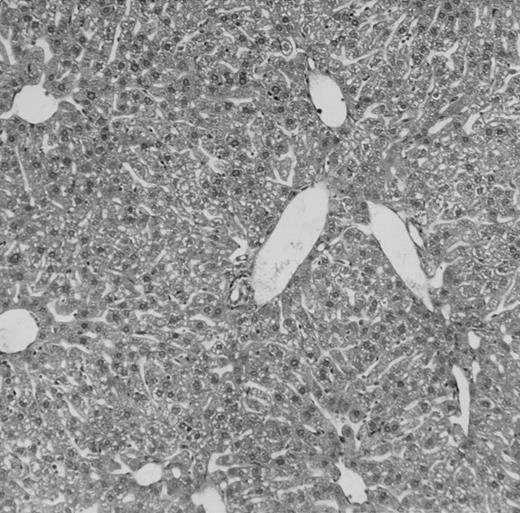

Histologic findings. Organs were collected at different times after BMT and tissue sections were stained with hematoxylin and eosin. Original magnifications for spleen (left) and liver (right) are ×40 and ×100, respectively. (A) B6 mice receiving FVB BM plus EpTK T cells. (B) Control group receiving BM only.

(C) B6 mice receiving FVB BM plus EpΔTK T cells and treated with GCV. (D) B6 mice receiving FVB BM plus EpΔTK T cells, treated with GCV, and developing a late onset GVHD (day 54).

FVB BM-grafted B6 mice: a model of lethal GVHD.We developed a model of GVHD resulting in 100% mortality soon after BMT using FVB mice, a strain not previously used as BM donors in experimental allogeneic BMT. We tested different combinations of recipient irradiation doses, as well as injected BM cell and CD3+ peripheral T-cell numbers. When 10-Gy–irradiated B6 mice were reconstituted with 107 FVB BM cells, we observed prolonged survival, whereas all ungrafted animals died before day 16 (Fig 2). In these conditions, more than 98% of splenocytes were of donor origin (Fig 3A). When 107 CD3+ peripheral T cells from mice of FVB genetic background were added to the FVB BMT, all animals died of GVHD between days 7 and 34 (Fig 2). Similar results were obtained using either PBS-treated mice receiving EpTK or EpΔTK peripheral T cells or GCV-treated mice receiving FVB nontransgenic peripheral T cells. Notably, this observation also indicates that both TK- and ΔTK-expressing T cells in the absence of GCV are fully competent to induce a lethal GVHD. Histopathologic examination of spleen and liver of these animals showed characteristic GVHD lesions such as (1) architecture disruption, necrosis, and congestion in the spleen; (2) hepatic periportal necrosis; (3) mononuclear portal infiltrates; and (4) endothelialitis of portal or centrolobular veinules (Fig 4A). By comparison, B6 mice receiving only FVB BM had a normal histology (Fig 4B).

Protection from GVHD was slightly less efficient in the group receiving EpΔTK CD3+ T cells. The survival rate was 79% at day 60 and 67% at day 120 (Fig 2B). However, two different outcomes must be distinguished. On the one hand, a majority of mice behaved as GCV-treated animals receiving EpTK T cells. They were apparently healthy, presented no skin lesions during a 120-day observation period, and showed complete donor-type hematologic reconstitution. There were no histological signs of GVHD in the spleen or liver (Fig 4C).

On the other hand, 5 of 19 mice exhibited signs suggesting the occurrence of a delayed GVHD (Table 1). Clinically, these animals presented weight loss and/or skin lesions on ears, neck, limbs, or abdomen, but only after day 40. In the absence of any further GCV treatment, 2 mice died 14 and 29 days after the occurrence of these signs (Table 1A) with histological signs of severe GVHD (Fig 4D). These results suggest that, in these mice, the 7-day GCV treatment was sufficient to prevent early, but not delayed GVHD.